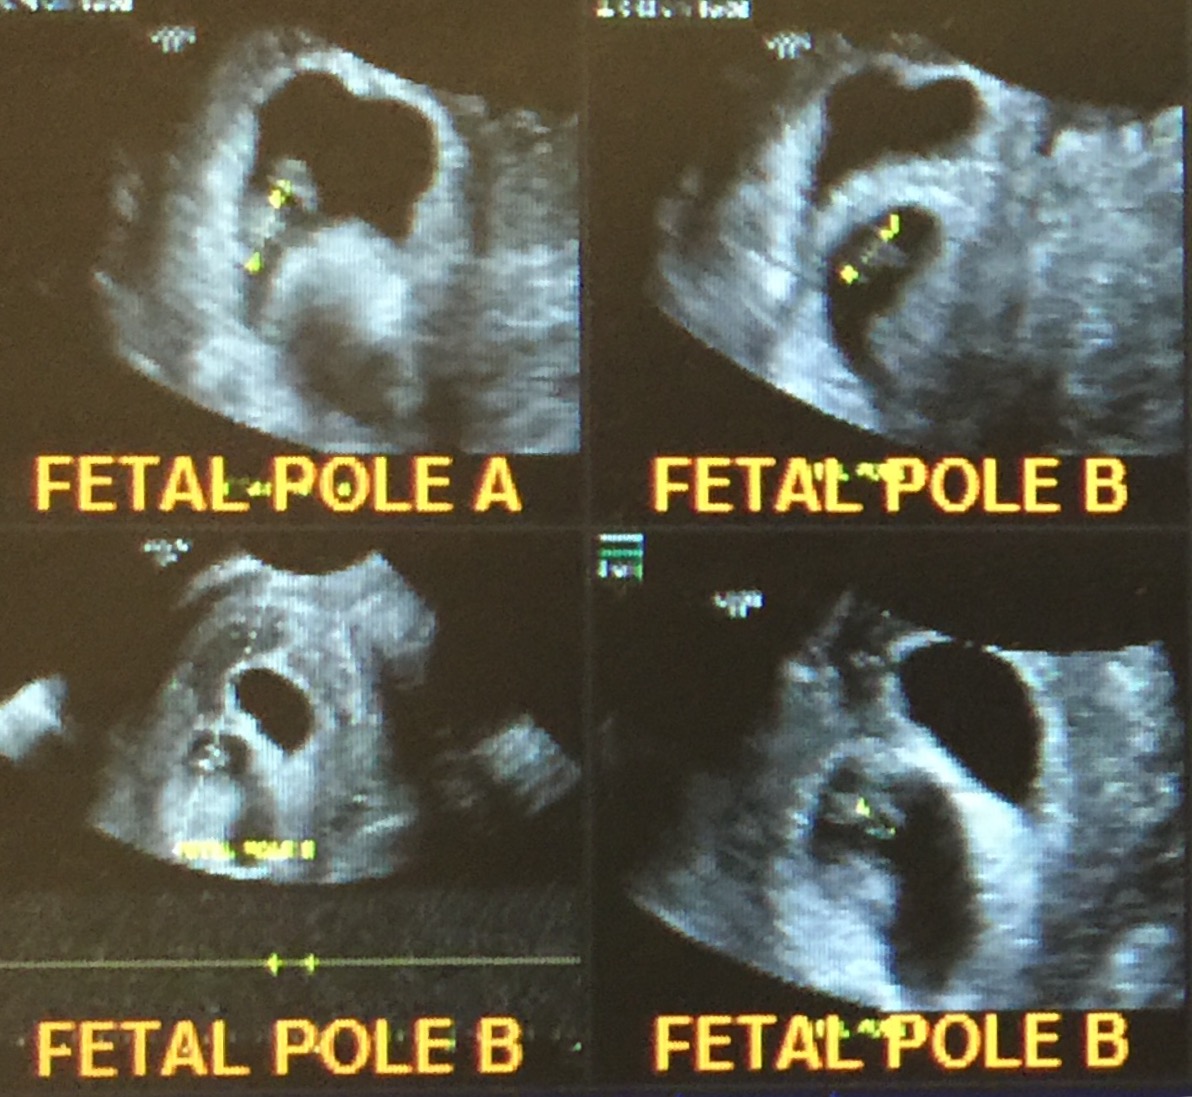

I just found out yesterday I am carrying fraternal twins. One heart beat is not visible at 8weeks. They said I could be earlier than we think. They said there is hope and to wait another week and see if it developed. Anyone have experience or advice with this? I have had a previous mc and I had bleeding a couple weeks ago. It was about a small tampon full, but it stopped pretty quickly. I'm trying not to be emotional either way, but you know.

8 week ultrasound and there's twins! We were only able to see one heart beat and they thought I'm a week behind where I thought I was so please send good growing thoughts my way. Headed back in a week to hear Baby B. also if anyone has had experience in this area, please advise.

8 week ultrasound and there's twins! We were only able to see one heart beat and they thought I'm a week behind where I thought I was so please send good growing thoughts my way. Headed back in a week to hear Baby B. also if anyone has had experience in this area, please advise.</p>